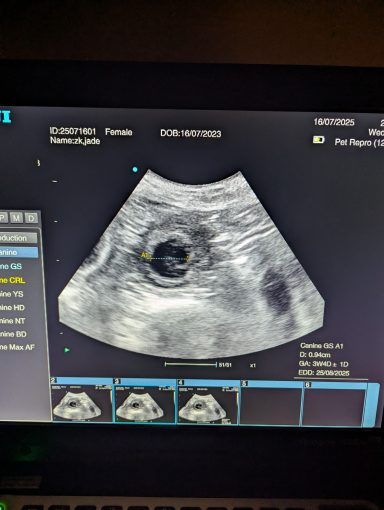

Ultrasound pregnancy scanning is a safe, non-invasive way to confirm pregnancy in dogs and cats, offering breeders and pet owners peace of mind and vital information to support responsible care. It allows us to detect gestational sacs, assess foetal development, and estimate litter size—all while ensuring the wellbeing of the animal.

Pregnancy can sometimes be detected as early as Day 18 post-mating, but scanning at this stage is not routinely recommended. Embryos are still developing and may not be clearly visible, and there is a natural risk of embryo resorption, which can lead to misleading or inconclusive results.

For the most accurate and reliable scan, we advise booking between Day 25 and Day 32, when pregnancy is more easily confirmed and foetal structures are clearer. If an early scan is performed and no pregnancy is detected, we offer a FREE complimentary re-scan after 7 days at the clinic to ensure clarity and support informed decision-making.